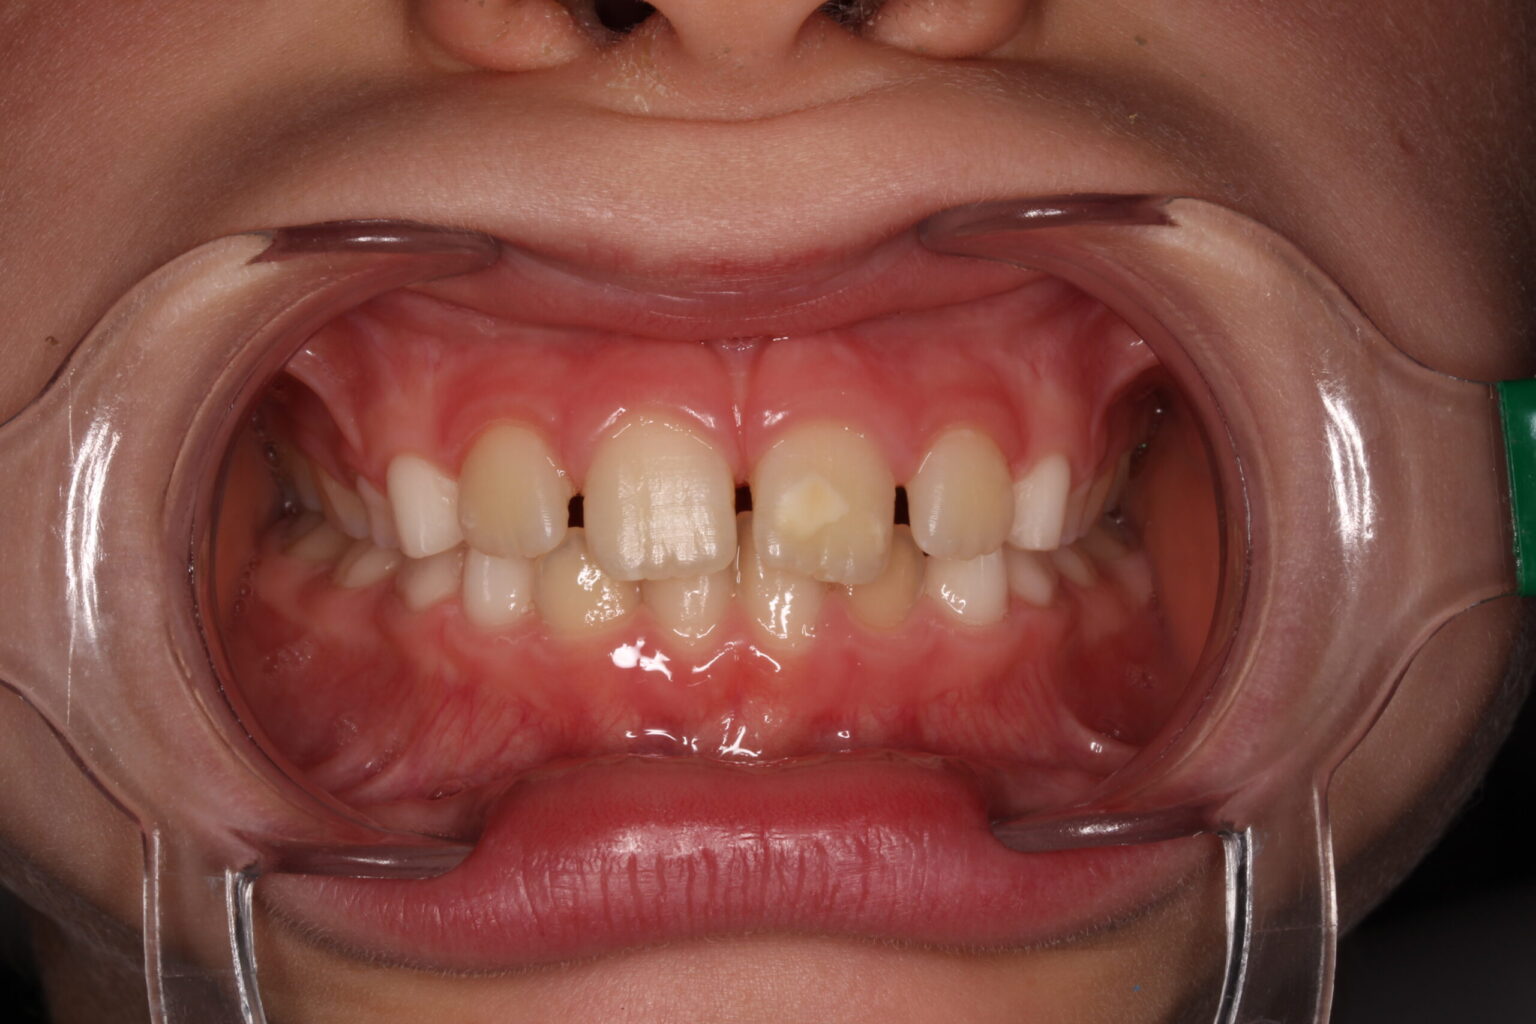

From dmg-connect.com

Resin Infiltration in the Treatment of MIH Lesions in Anterior Teeth in Mih Dental Causes The cause is not fully known. Molar incisor hypomineralisation (mih) is a developmental defect of enamel causing cream, yellow or brown opacities on. Molar incisor hypomineralization (mih) is a significant health problem that can affect the child’s quality of life by negatively affecting their esthetics and function. Mih is a worldwide problem. Around 1 in 8 children in the uk. Mih Dental Causes.